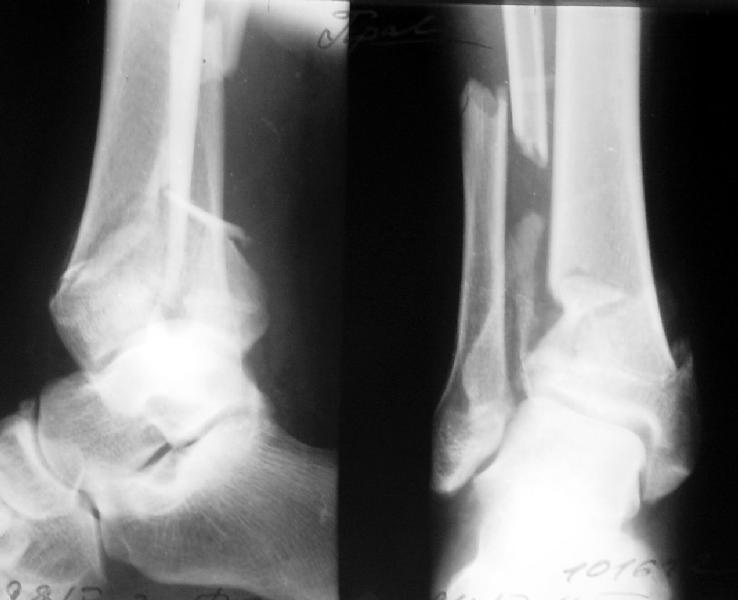

Отправитель: Alexander Chelnokov 07 Август 2003, 12:54

> 1. Whould be interesting to see pre-op X ray.

Attached.

Кликните для загрузки файла get_image.jpg